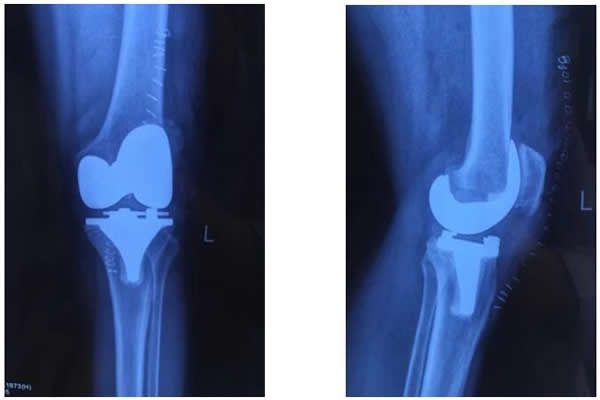

白奶奶今年72歲,雙膝關(guān)節(jié)疼痛10余年。近兩年來,雙膝疼痛加重,經(jīng)多方治療沒有任何效果,雙下肢也逐漸呈明顯的“O型腿”。近期疼痛加重,行走困難,這讓白奶奶的家人非常著急,為解除病痛,白奶奶一家慕名前來西電集團(tuán)醫(yī)院骨科就診。經(jīng)該院骨科張富軍主任詳細(xì)診查,雙膝拍片確診患有:雙膝關(guān)節(jié)骨性關(guān)節(jié)炎合并雙側(cè)內(nèi)翻屈曲畸形。為提高生活質(zhì)量,解除病痛,建議進(jìn)行同期雙膝人工關(guān)節(jié)置換手術(shù)。

術(shù)前,骨科主任張富軍、主治醫(yī)師張浩為患者制定了嚴(yán)格的治療方案,經(jīng)過2周的術(shù)前準(zhǔn)備感染指標(biāo)降至正常,于2017年1月13日在手術(shù)室、麻醉科等相關(guān)科室的周密配合下,由張富軍主任、張浩主治醫(yī)師、何鵬主治醫(yī)師、裴海波醫(yī)師為白奶奶進(jìn)行同期雙側(cè)人工膝關(guān)節(jié)表面置換手術(shù),麻醉由龐曉紅主任、劉文雄醫(yī)師擔(dān)任,手術(shù)順利,手術(shù)歷時(shí)2.5小時(shí),術(shù)后恢復(fù)滿意,術(shù)后第1天白奶奶已能下床行走,術(shù)后第6天行走出院,白奶奶對手術(shù)效果非常滿意并讓家人為骨科送來了錦旗表示感謝。